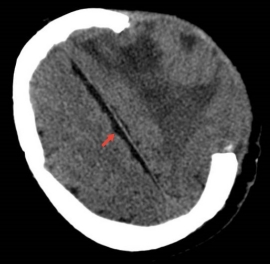

对于因严重颅脑损伤或脑出血而行去骨瓣减压术的患者而言,术后至颅骨修补手术前的1-3个月是尤为脆弱且焦虑的时期,医学上称之为“空窗期”。此阶段,患者颅骨存在大面积缺损,大脑仅靠头皮保护,不仅面临外力冲击导致二次损伤的高风险,还可能并发硬膜下积液等并发症。传统通用型保护头盔普遍存在贴合度差、易压迫头部、闷热不透气、外观不美观等诸多不足,不仅影响患者佩戴体验,更加重了其心理负担。

为破解这一难题,神经外科郑攀医师团队创新性地将3D打印技术应用于颅骨缺损的临时性防护。团队通过采集患者术后的薄层CT数据,利用三维重建与AI智能技术,为每一位患者“量体裁衣”,精准打印出与其颅骨缺损形态完美契合的个性化保护帽。

目前,该项目已成功应用于多位患者。临床案例显示,此个性化保护帽不仅提供了优异的外部防护,还在一定程度上辅助稳定了颅内环境,对促进硬膜下积液吸收、为二期手术创造良好条件展现出积极效果。患者满意度调查结果显示,其在舒适度、安全感和便利性方面均获得高度评价。

佩戴2周后硬膜下积液消失